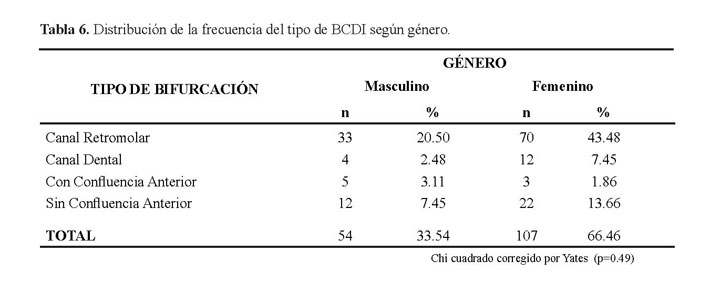

No hubo diferencia estadísticamente significativa entre el género femenino y masculino (p=0.49) (Tabla 6).

La tabla 8 muestra la distribución del género de pacientes con bifurcación del conducto dentario inferior. En la revisión de la literatura algunos investigadores han reportado una ligera predilección por el sexo femenino para la incidencia de la BCDI mediante radiografías panorámicas teniendo en cuenta el total de pacientes evaluados,sin embargo en nuestro estudio no hubo diferencia estadísticamente significativa entre ambos sexos.